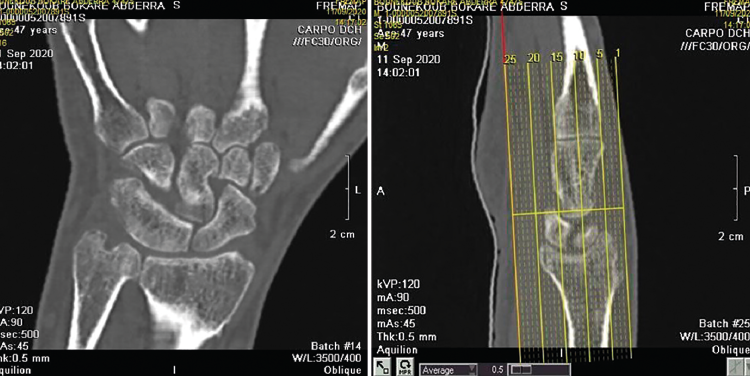

Se solicitan estudios de imagen. En primer lugar, rayos X de muñeca en proyección anteroposterior (AP) (Figura 1), en los que se evidencia un aumento del espacio cubital y presencia de la fusión lunopiramidal. Se coloca una inmovilización con muñequera elástica. Se solicita (Figura 2) tomografía axial computarizada (TAC) para la confirmación del diagnóstico y resonancia magnética (RM) (Figura 3) de mano para valorar las estructuras blandas. Los hallazgos de la TAC reportan la coalición lunopiramidal de tipo Minnaar III y la RM realizada para valorar lesiones asociadas de partes blandas reporta sinovitis. El resto de los elementos no muestran alteraciones.

Figura 3. Imagen de resonancia magnética de muñeca y mano.